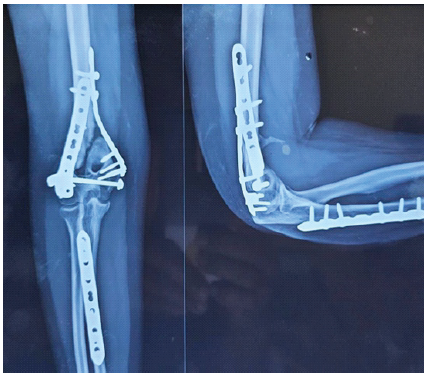

A woman in her 30s from South Asia presented to our tertiary orthopedic unit with persistent pain, restricted range of motion, and functional impairment in her left upper limb. These symptoms had been present for several months following surgical fixation of a distal humerus intercondylar fracture sustained after a fall on an outstretched hand while descending stairs. At the time of injury, she was evaluated at a local trauma center, where radiographs revealed a displaced intercondylar distal humerus fracture with a concurrent fracture of the proximal shaft of the ipsilateral ulna (Fig. 1). She underwent open reduction and internal fixation using dual plating for the distal humerus and plating for the ulnar fracture (Fig. 2). The limb was immobilized in a splint for 10 days, followed by supervised physiotherapy. The ulnar fracture showed progressive healing and achieved union by 3 months post-operatively.

Figure 2: Immediate post-operative anteroposterior and lateral radiographs showing stable dual-plate fixation of the distal humerus with associated plate fixation of the ipsilateral ulna.